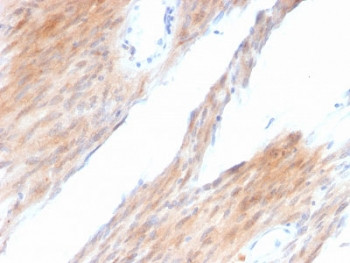

Product information "Anti-c-Kit / CD117, clone KIT/2674"

Prediluted in 1X PBS with 0.1 mg/ml BSA (US sourced) and 0.05% sodium azide, *For IHC use only*. This mAb recognizes a protein of 145kDa, identified as CD117/p145kit/c-Kit. It is found on a wide variety of tumor cells including follicular and papillary carcinoma of thyroid, adenocarcinomas from endometrium, lung, ovary, pancreas, and breast as well as malignant melanoma, endodermal sinus tumor, and small cell carcinoma. However, anti-CD117 has been particularly useful in differentiating gastrointestinal stromal tumors from Kaposi s sarcoma, tumors of smooth muscle origin, fibromatosis, and neural tumors of the GI tract. Anti-CD117 is also useful in recognizing myeloblasts in bone marrow biopsy and clot section. Protein function: Tyrosine-protein kinase that acts as cell-surface receptor for the cytokine KITLG/SCF and plays an essential role in the regulation of cell survival and proliferation, hematopoiesis, stem cell maintenance, gametogenesis, mast cell development, migration and function, and in melanogenesis. In response to KITLG/SCF binding, KIT can activate several signaling pathways. Phosphorylates PIK3R1, PLCG1, SH2B2/APS and CBL. Activates the AKT1 signaling pathway by phosphorylation of PIK3R1, the regulatory subunit of phosphatidylinositol 3-kinase. Activated KIT also transmits signals via GRB2 and activation of RAS, RAF1 and the MAP kinases MAPK1/ERK2 and/or MAPK3/ERK1. Promotes activation of STAT family members STAT1, STAT3, STAT5A and STAT5B. Activation of PLCG1 leads to the production of the cellular signaling molecules diacylglycerol and inositol 1,4,5-trisphosphate. KIT signaling is modulated by protein phosphatases, and by rapid internalization and degradation of the receptor. Activated KIT promotes phosphorylation of the protein phosphatases PTPN6/SHP-1 and PTPRU, and of the transcription factors STAT1, STAT3, STAT5A and STAT5B. Promotes phosphorylation of PIK3R1, CBL, CRK (isoform Crk-II), LYN, MAPK1/ERK2 and/or MAPK3/ERK1, PLCG1, SRC and SHC1. [The UniProt Consortium]

| Application: | IHC (paraffin) |